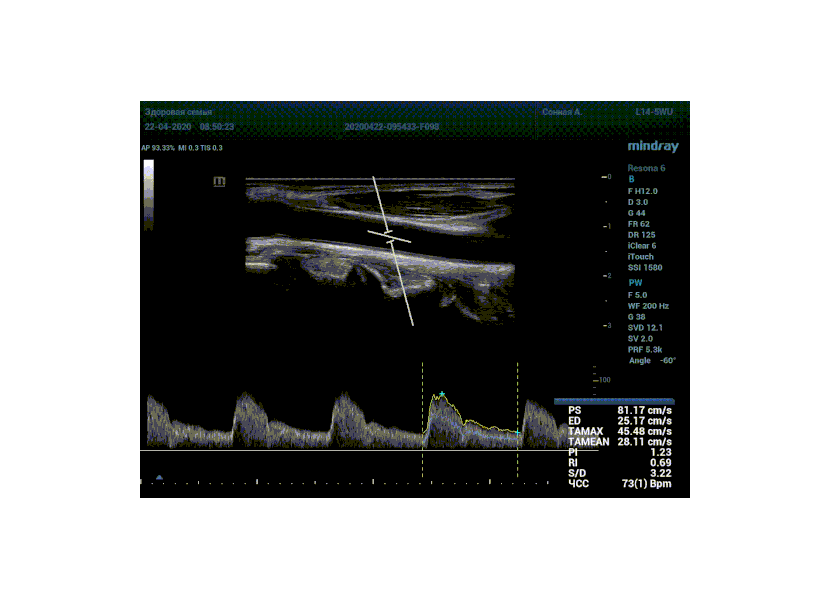

Какие показатели выдает автоматический расчет? Доктор может настроить расчет под себя, под свои собственные желания. Стандартно выставлены показатели пиковой (PS) и конечной диастолической скорости (ED), TAMAX, TAMEAN, Pi, Ri, S/D соотношение и ЧСС. Можно дополнить из списка показателей: MD, PPG, Объемный поток, DT, AT, MPG, MMPG, VTI, D/S соотношение. Прибор подстраивается под Вас, а не вы под прибор.